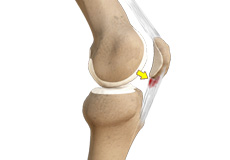

Jumper's Knee

Jumper’s knee, also known as patellar tendinitis, is inflammation of the patellar tendon that connects your kneecap (patella) to your shinbone. This tendon helps in the extension of the lower leg.